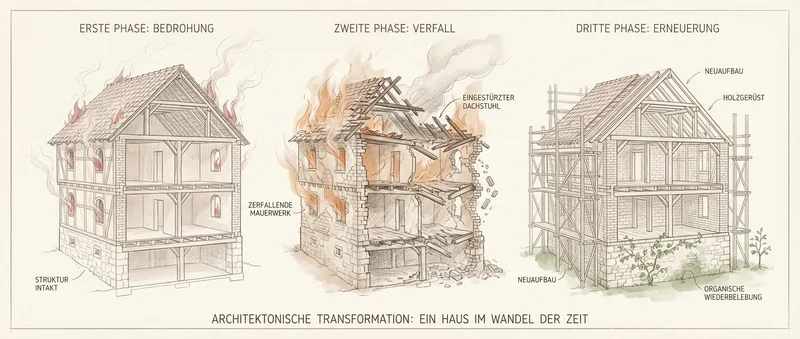

„Stellen Sie sich vor, Ihr Gelenk ist ein Haus, das brennt.

Was machen die meisten Therapien? Sie liefern Baumaterial — Glucosamin, Kollagen, Chondroitin. Aber das Haus brennt ja noch. Das Material verbrennt, bevor es ankommt.

Und die Schmerzmittel? Die schalten nur den Rauchmelder aus. Das Feuer brennt weiter — schlimmer als zuvor. Sie merken es nur nicht mehr."

Monika sah ihn an. „Und was müsste man stattdessen tun?"

„Erst die Feuerwehr rufen."

Die Entzündung löschen — aber nicht mit Ibuprofen, das den Knorpel austrocknet. Sondern mit natürlichen Entzündungshemmern, die den Knorpel nicht angreifen.

„Und dann den Architekten."

Erst wenn der Brand gelöscht ist, kann der Aufbau beginnen. Erst dann kann der Knorpel wieder Nährstoffe aufnehmen.

Feuerwehr, dann Architekt.

In dieser Reihenfolge. Nicht andersherum. Nicht gleichzeitig. Und ganz sicher nicht nur den Rauchmelder ausschalten.

„Den Rauchmelder ausschalten"

Schmerzmittel stoppen das Signal — nicht das Problem. Ibuprofen hemmt die Moleküle, die den Knorpel feucht halten.

Ergebnis: Knorpel trocknet aus. Das Gelenk wird schlechter.

„Baumaterial ins brennende Haus"

Glucosamin, Kollagen, Chondroitin — einzeln und gut gemeint. Aber solange die Entzündung aktiv ist, kommt nichts davon an.

Ergebnis: Verbrennt, bevor es wirken kann.

„Erst die Feuerwehr. Dann der Architekt."

Schritt 1 — Löschen: Die Entzündung natürlich stoppen — ohne den Knorpel anzugreifen.

Schritt 2 — Aufbauen: Eierschalenmembran liefert alle Bausteine im Verbund — so wie der Körper sie erkennt.

Ergebnis: Aufbau statt Verfall.

„Den Rauchmelder ausschalten"

Schmerzmittel stoppen das Signal — nicht das Problem. Ibuprofen hemmt die Moleküle, die den Knorpel feucht halten.

Ergebnis: Knorpel trocknet aus. Das Gelenk wird schlechter.

„Baumaterial ins brennende Haus"

Glucosamin, Kollagen, Chondroitin — einzeln und gut gemeint. Aber solange die Entzündung aktiv ist, kommt nichts davon an.

Ergebnis: Verbrennt, bevor es wirken kann.

„Erst die Feuerwehr. Dann der Architekt."

Schritt 1 — Löschen: Die Entzündung natürlich stoppen — ohne den Knorpel anzugreifen.

Schritt 2 — Aufbauen: Eierschalenmembran liefert alle Bausteine im Verbund — so wie der Körper sie erkennt.

Ergebnis: Aufbau statt Verfall.